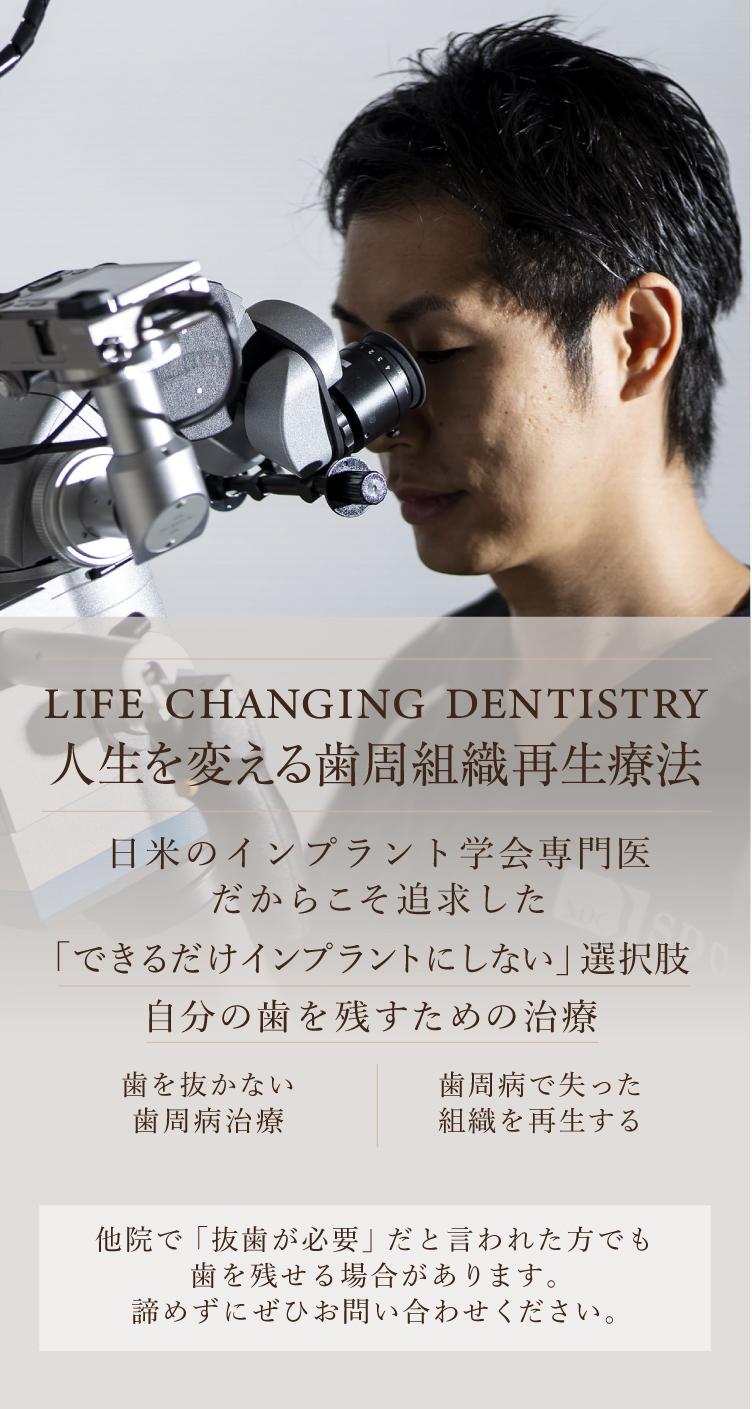

歯周組織再生療法は施術の難易度が高く、ほとんどの歯科では扱っていない内容です。

理事長の菅は日々新たな歯科治療の技術や知識を学び、それを臨床の現場に反映しています。再生療法の世界的な権威のDr. Cortellini 歯周組織再生治療のセミナーを受講。

また、トロント大学での1年間の根管治療スタディプログラムの受講や歯周再生マスターコース受講、テキサス大学ヒューストン校の歯周病コース修了、日本口腔インプラント学会専門医、AAID(アメリカのインプラントにおける最難関資格)の専門医資格を取得しております。

専門医資格を持つ医師が歯周組織再生治療を手がけるので、安心して治療を受けていただけます。